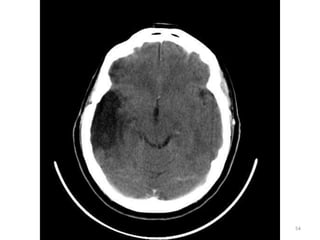

1. Fissura de Sylvios.

2. Foice do cérebro.

3. Terceiro ventrículo.

39

1. Corno Anterior do

Ventrículo lateral D.

2. Corpo caloso D.

4. Plexo coróide.

40